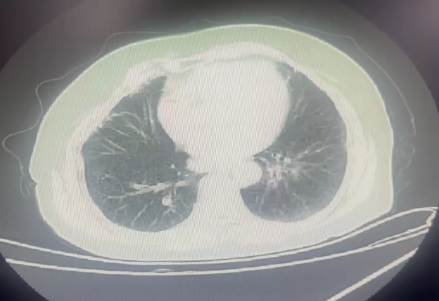

10月9日胸部 CT:双肺轻度间质改变伴纤维化。

11月18日肺部 CT